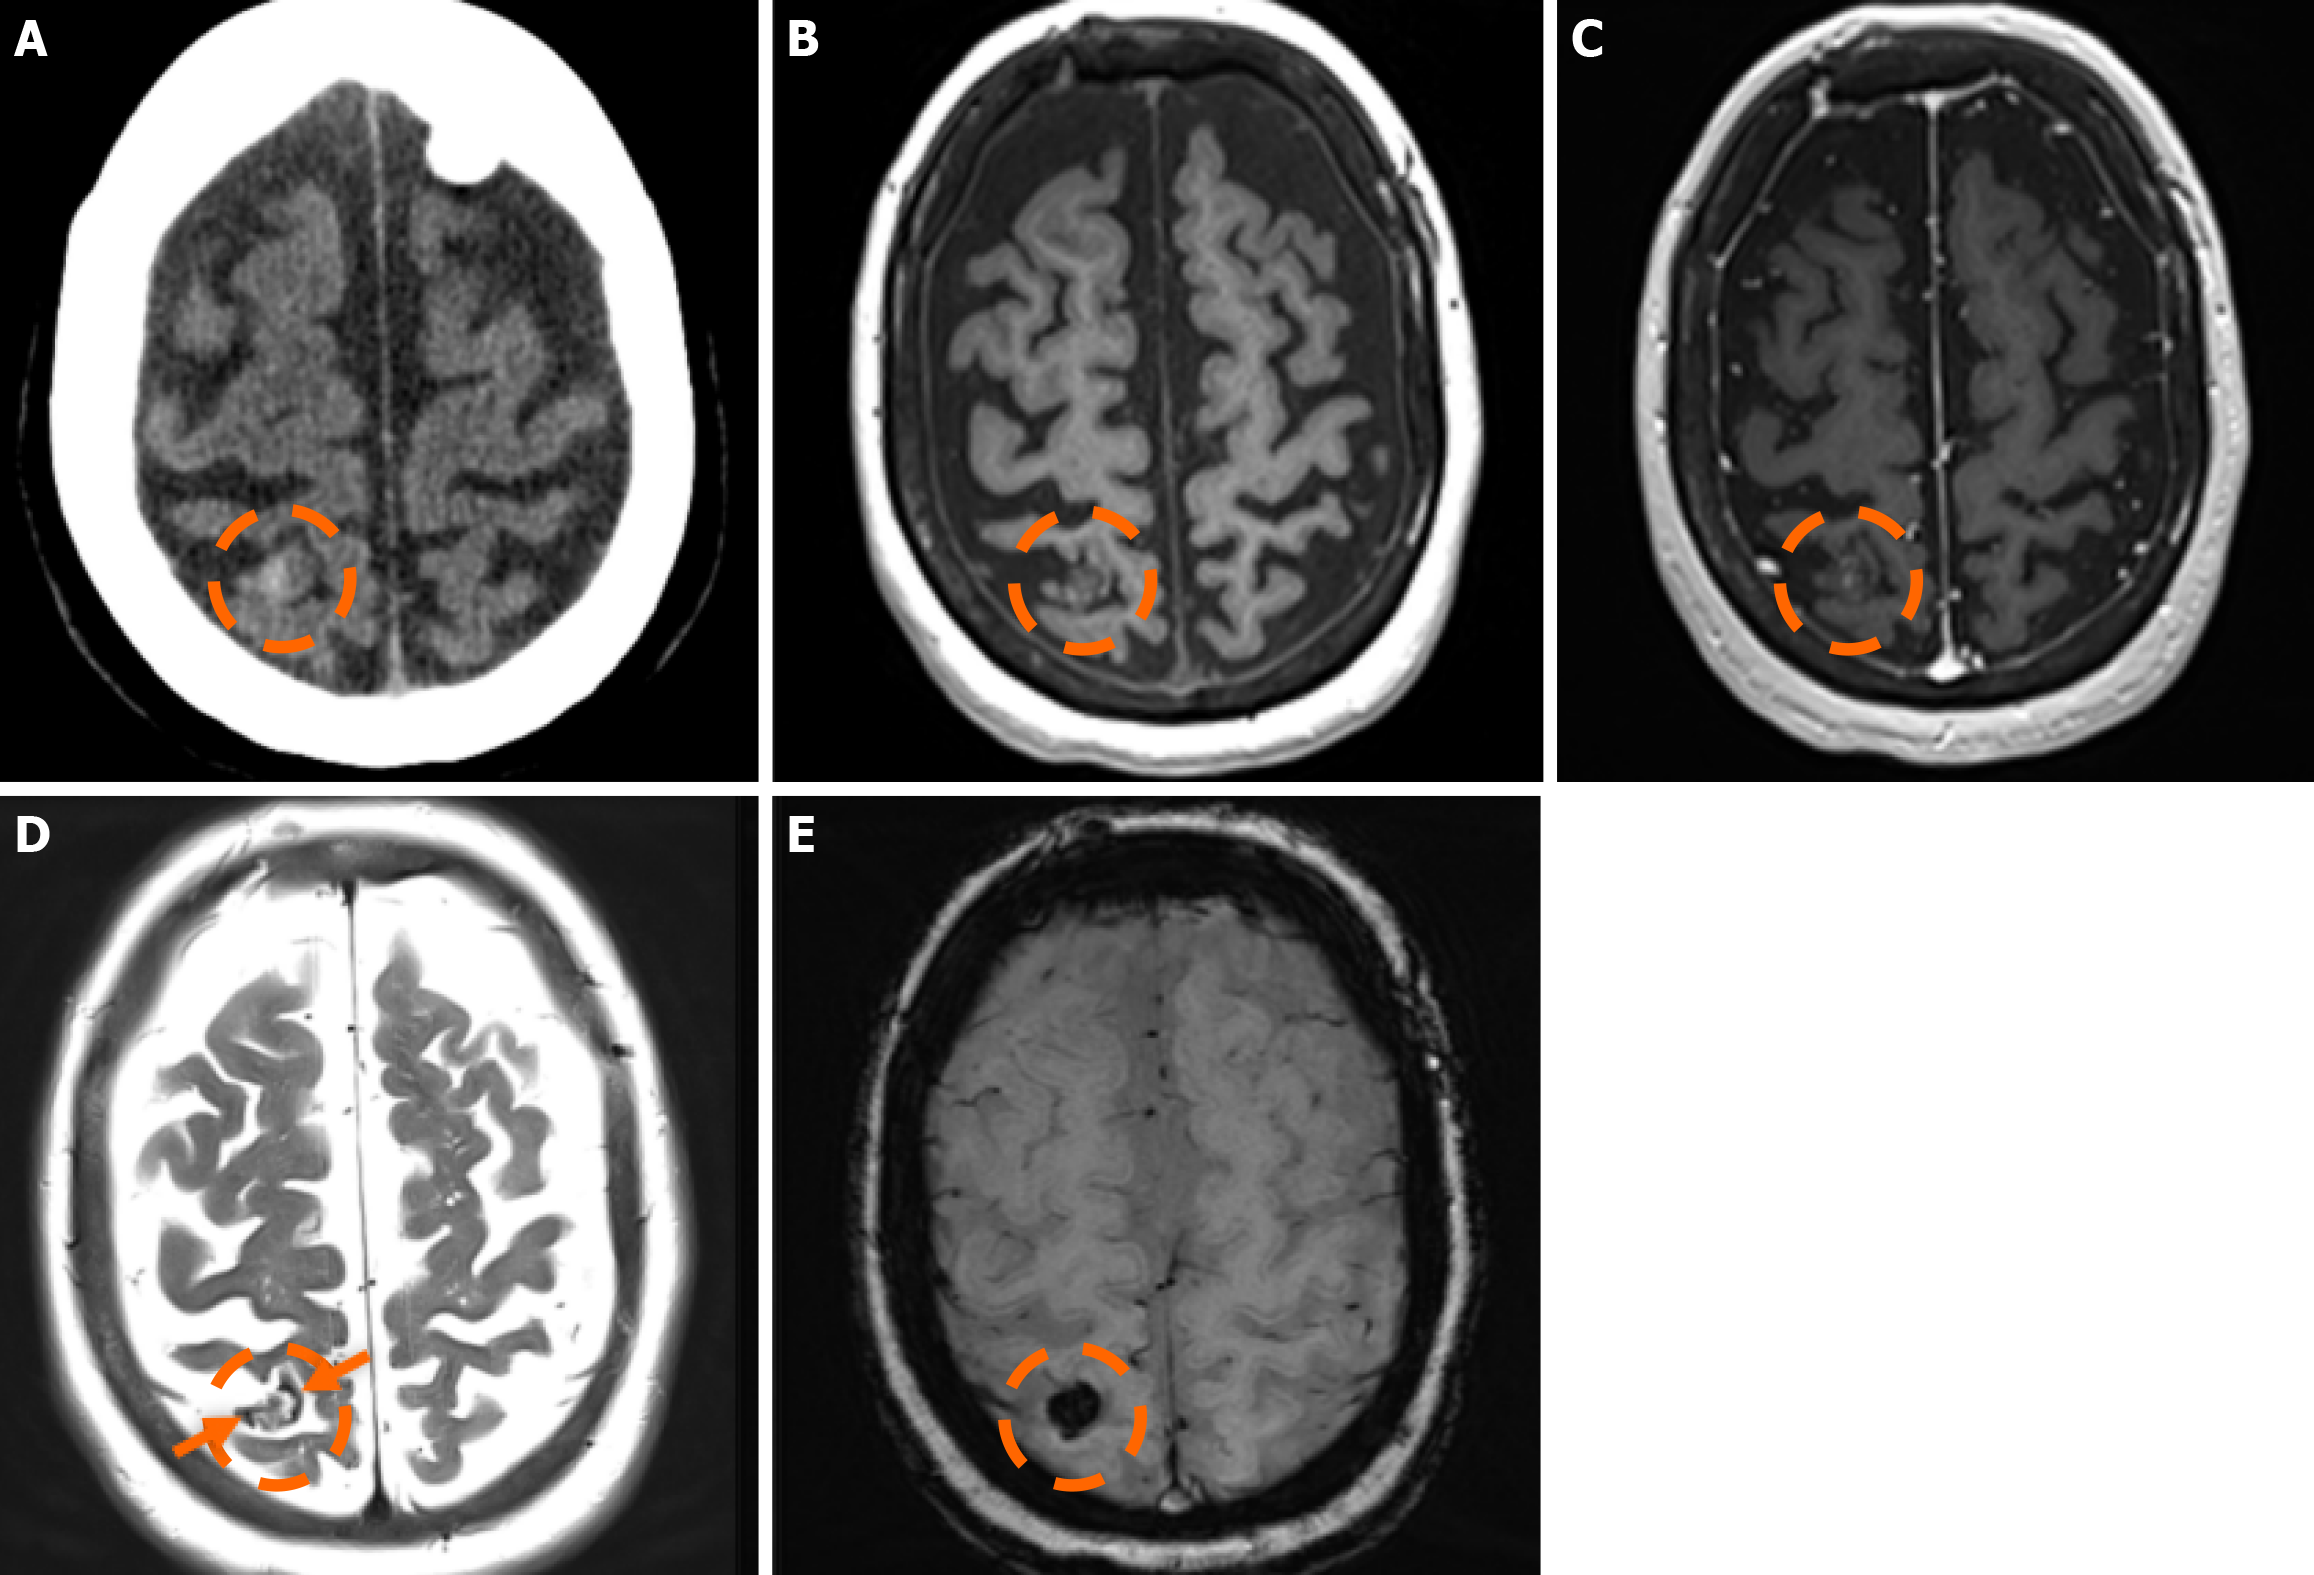

The clinical applicability of the Zabramski classification is still being investigated. A retrospective cohort study evaluating the imaging evolution and clinical trajectory of 255 untreated patients with sporadic CMs over a follow-up period of approximately five years provided evidence that the Zabramski classification may facilitate risk stratification and contribute to treatment planning, particularly in determining the necessity for surgical intervention[89]. Furthermore, a recent study by Saari et al[88] established an association between the radiological characteristics of the Zabramski classification and their clinical relevance, emphasizing that type I lesions have a higher likelihood of becoming symptomatic. Nikoubashman et al[90] suggested an additional category (type V lesions) accounting for cavernomas presenting with gross extralesional hemorrhage. Various examples of CMs on CTs and MRIs, including familial cerebral CM cases, are shown in Figures 4, 5 and 6.

The sensitivity of CT in detecting CMs is limited, with a detection rate ranging between 30% and 50%[79]. Sensitivity decreases significantly in smaller lesions (< 1 cm)[74,75]. CMs do not exhibit distinct imaging characteristics; they typically appear as well-defined lesions that may be either hypodense or hyperdense, depending on the presence of calcifications and hemosiderin deposits. Following contrast administration, mild enhancement may be observed. Edema or mass effect is uncommon unless a recent hemorrhage has occurred[80]. CT is typically the initial and preferred imaging modality in acute settings to rule out hemorrhage[81].

MRI remains the gold standard for detecting and further characterizing CMs[81]. Conventional MRI sequences, particularly T1w and T2w imaging, exhibit high sensitivity and specificity for identifying clinically symptomatic CMs[75]. Their signal characteristics on MRI vary depending on lesion size and hemorrhagic status. Small, punctate lesions typically appear hypointense on T2w imaging. In contrast, larger CMs exhibit a characteristic reticulated pattern of mixed hypo- and hyperintense signals, resembling the so-called “mulberry-like” or “popcorn” appearance on T2 and FLAIR sequences. Increased signal in T1 sequences reflects the presence of methemoglobin, indicative of subacute hemorrhage. A characteristic hypointense rim surrounding the lesion could also be noted. Usually, CMs lack prominent enhancement, while they could exhibit low to moderate enhancement, particularly if there is associated blood-brain barrier disruption, recent hemorrhage, or adjacent gliosis. Additionally, the presence of deoxyhemoglobin and hemosiderin results in susceptibility effects, leading to a decrease in signal intensity on T2w sequences. Thus, GE sequences and particularly T2*-weighted have proven valuable in the detection of CCMS. Multiple studies have demonstrated that T2w GE (GRE) imaging offers increased sensitivity compared to other MRI sequences for the detection of sporadic and familial cases of CM lesions[80].

SWI represents an advanced imaging technique particularly well-suited for the detection of VMs, owing to its high sensitivity to deoxyhemoglobin and iron deposition. SWI has demonstrated higher sensitivity compared to GRE imaging in the detection of CMs, especially in familial cases[82,83]. Moreover, SWI also provides enhanced sensitivity for the detection of associated venous anomalies and potential telangiectasias, especially in cases where contrast media is contraindicated[84]. Nevertheless, the hemosiderin-induced “blooming effect” could artifactually exaggerate the apparent size of the lesions; thus, both GRE and SWI sequences should be interpreted carefully[84]. Additionally, small hemor

In 1994, Zabramski et al[87] proposed an MRI-based classification system for CMs, based on their imaging characteristics, particularly on T1w, T2w, and susceptibility-sensitive sequences, which remains one of the most widely used methods for characterizing these lesions. The classification system is outlined in Table 1.

Type I lesions exhibit a hyperintense core on T1w imaging, indicative of subacute hemorrhage due to methemoglobin accumulation. The lesion’s size and intensity may fluctuate over time, reflecting the dynamic nature of the hemorrhagic process[88]; Type II lesions, considered the most prevalent type, exhibit the classic “popcorn-like” imaging, displaying a heterogeneous core with mixed signal intensities on both T1w and T2w sequences and a well-defined hypointense hemosiderin ring on T2-GRE or SWI images; Type III lesions represent chronic hemosiderotic lesions, appearing hypointense or isointense on T1w and T2w MRI, demonstrating ‘’blooming effect’’ on T2-GRE or SWI, indicating prior hemorrhagic activity; and Type IV lesions include small punctate lesions, mainly visualized on susceptibility-sensitive sequences (T2-GRE or SWI). Classifying lesions as type IV could be challenging, as their exact pathological nature has not been definitively determined[85].